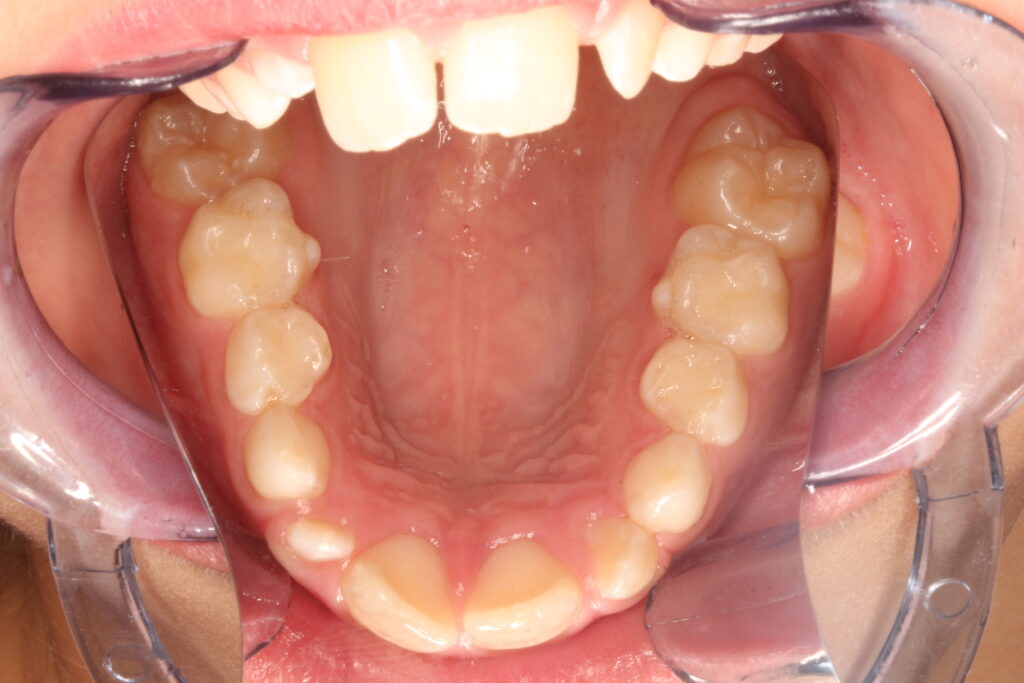

Az ALF készülék nem az agresszív erőhatásokra, hanem a funkcionális erők finom, biológiailag kíméletes irányítására épít. A klinikai tapasztalatok szerint ez tökéletes elég és mind a fogív fejlesztésében, keresztharapások megszűntetésében, helyteremtésben mind a nyelvtér növelésében jól működik.

A leggyakoribb a vegyes fogazat időszakában (6–11 év), de alkalmazható teljes tejfogazatban is nagyon korai kezelések esetében, akár 3-4 éves kortól is.